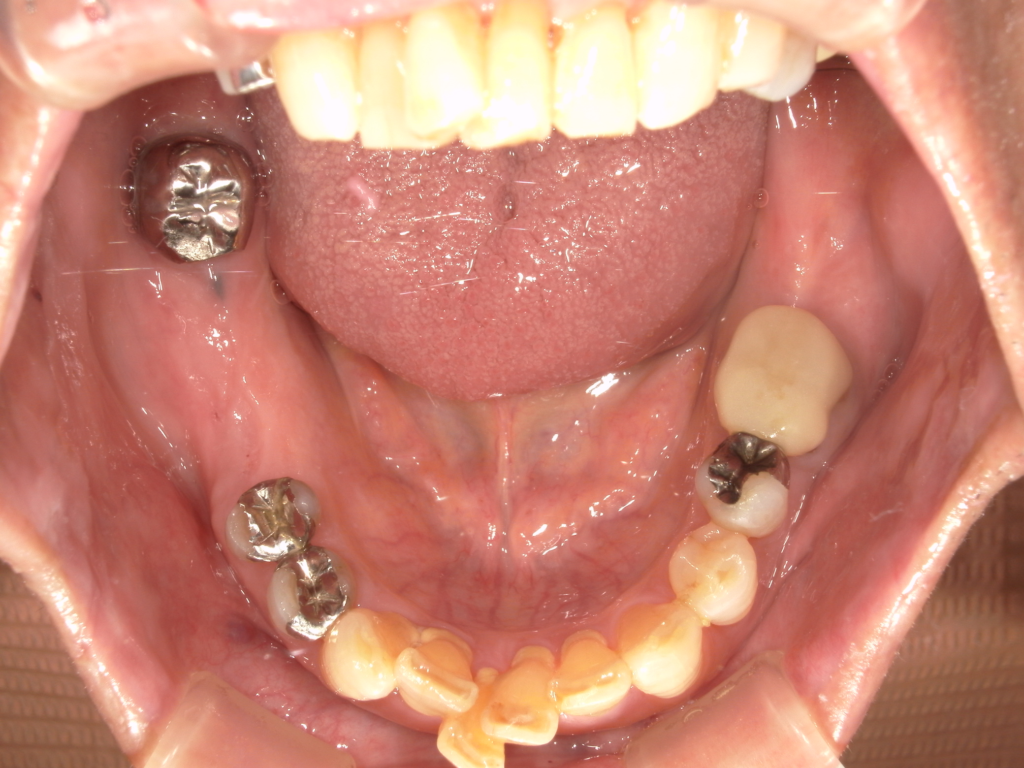

Y様インプラント実例 #44

左の上下の奥歯をインプラントで治療しています。

左下の奥歯は歯を抜くのと同時にインプラントの埋め込みを行っています。

被せものは上下、セラミックスで作っています。

治療前

治療後